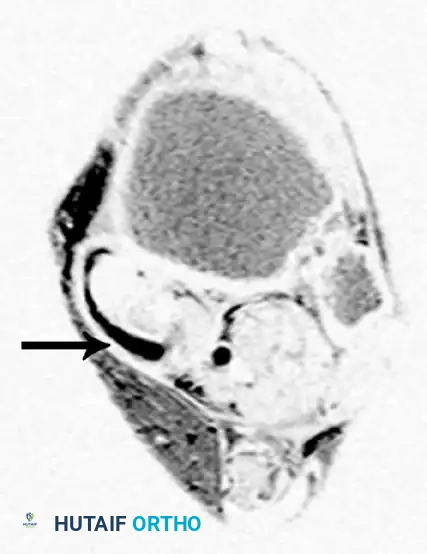

Magnetic Resonance Imaging (MRI)

MRI is highly sensitive for evaluating the integrity of the PTT, spring ligament, and deltoid ligament. T2-weighted and fat-suppressed images excel at demonstrating peritendinous effusions, tendinosis, and interstitial tearing. DeOrio et al. described the "posterior tibial edema sign," where subcutaneous pitting edema along the tendon correlates with MRI evidence of disease in 88% of patients.

Axial MRI slices demonstrating severe tendinosis, fluid within the tendon sheath, and attenuation of the spring ligament complex.